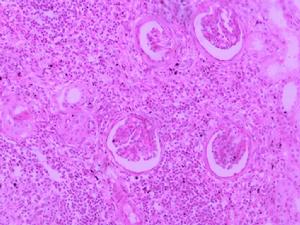

病理改變

急性腎盂腎炎病變可為單側或雙側,局限或廣泛,可輕可重,輕者僅累及腎盂黏膜。重者腎臟腫大,切面可見黏膜充血潰瘍,小膿腫形成。如伴梗阻,則腎盞增寬,少數嚴重患者,其腎乳頭及錐體部可見壞死,壞死組織隨尿液排出稱壞死性乳頭炎,鏡下可見腎間質水腫,嗜中性粒細胞浸潤。 慢性腎盂腎炎腎盂及腎盞有慢性炎症表現。腎盂擴大、畸形,腎皮質及乳頭部有瘢痕形成,腎臟較正常縮小,兩側病變常不對稱,腎髓質變形,腎盂腎盞黏膜及輸尿管管壁增蚅,嚴重者腎實質廣泛萎縮。